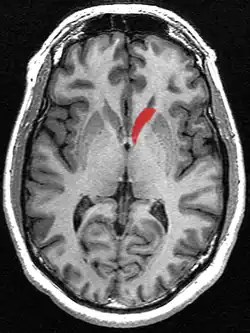

Transverse cut of brain (horizontal section), basal ganglia is blue | |

Along with the putamen, the caudate forms the dorsal striatum, which is considered a single functional structure; anatomically, it is separated by a large white-matter tract, the internal capsule, so it is sometimes also described as two structures—the medial dorsal striatum (the caudate) and the lateral dorsal striatum (the putamen). In this vein, the two are functionally distinct not because of structural differences, but merely because of the topographical distribution of function.